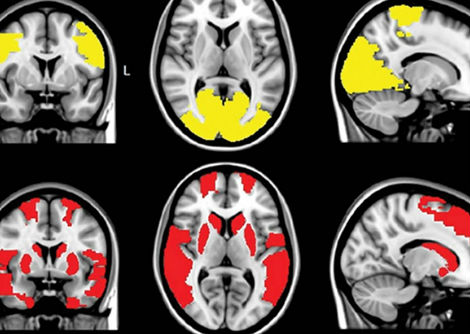

إجمالاً ، وجد الباحثون روابط قوية بين 19 نمطًا ظاهريًا وخمسة VNTRs مميزة . تشمل الخصائصُ المحتملة ذات الصلة بالصحة المتأثرة بـ VNTRs ارتفاعَ مستويات البروتين الدهني (أ) ، وعامل خطر رئيسي لمرض الشريان التاجي ، والعديد من السمات المرتبطة بوظيفة الكلى ، بما في ذلك النقرس وزيادة مستويات اليوريا في الدم .

كان الطول من أوضح الإشارات . أظهرت الدراسة أن اختلاف طول VNTR في الجين ACAN - والذي يرمز للبروتين aggrecan - ارتبط بمتوسط اختلاف في الطول بين الناس يبلغ 3.2 سم . تم اكتشاف VNTRs الأطول في الدراسة بأكثر من ضعف حجم المجال aggrecan ، وهو معروف من الدراسات السابقة لتمكين التعديلات الكيميائية التي تساعد المصفوفة خارج الخلية على الاحتفاظ بالماء . لكن الباحثين يقولون إنه ليس من الواضح كيف يمكن أن يؤثر هذا الاختلاف في قدرة الاحتفاظ بالمياه على الطول .